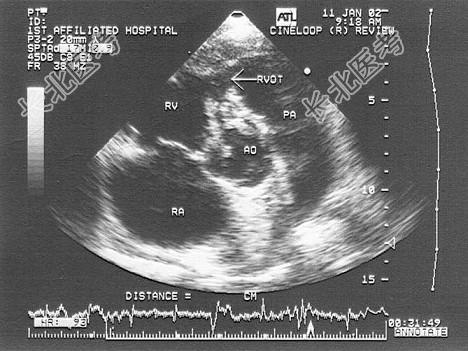

- 单项选择题患者反复发热,原有先心病史, 该病例最有可能诊断为   (   )

B、室缺并感染性心内膜炎